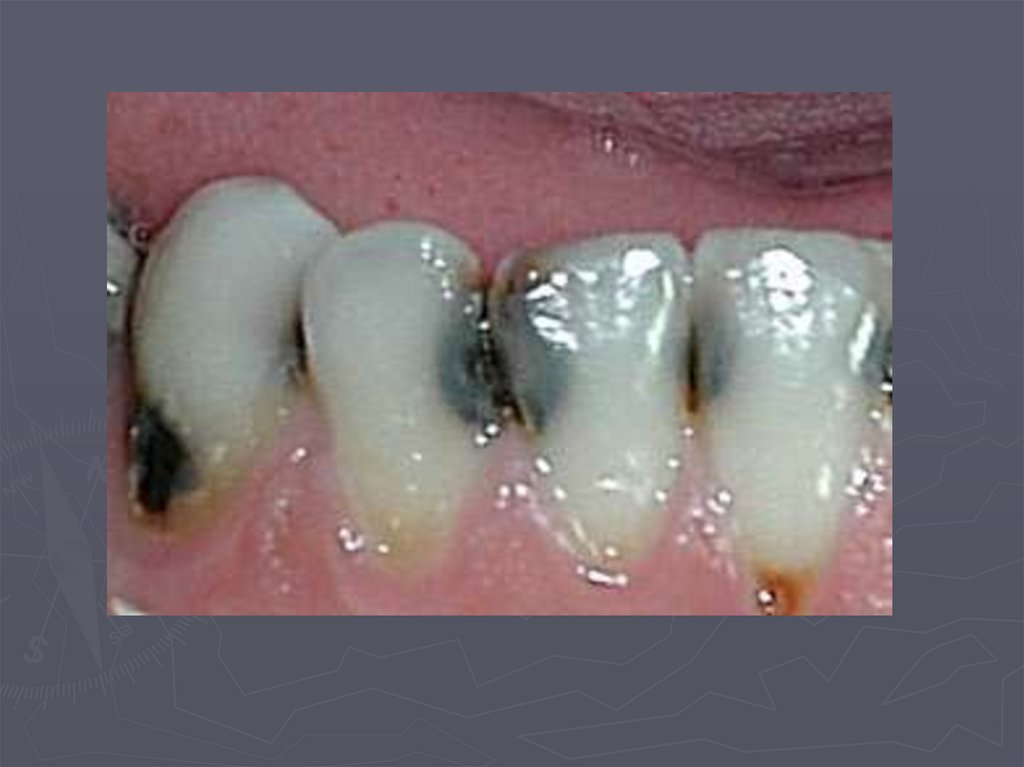

При клиническом осмотре выявляются:

► кариозные полости по глубине мелкие;

► имеют плоскую форму;

► входное отверстие в кариозную полость широкое

► эмаль по краям кариозной полости хрупкая;

► инфицированный дентин в полости влажный.

,